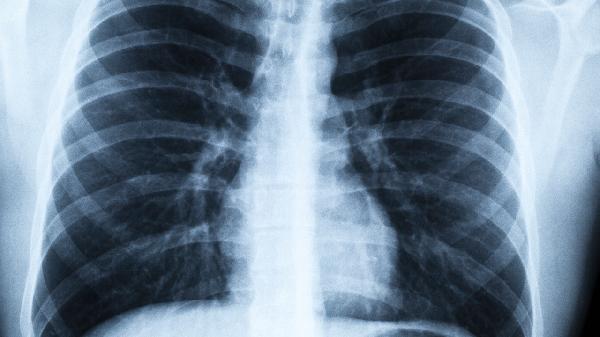

1、低剂量CT检查

相比胸片,低剂量CT能发现更小的肺部结节,是国际公认的肺癌筛查金标准。